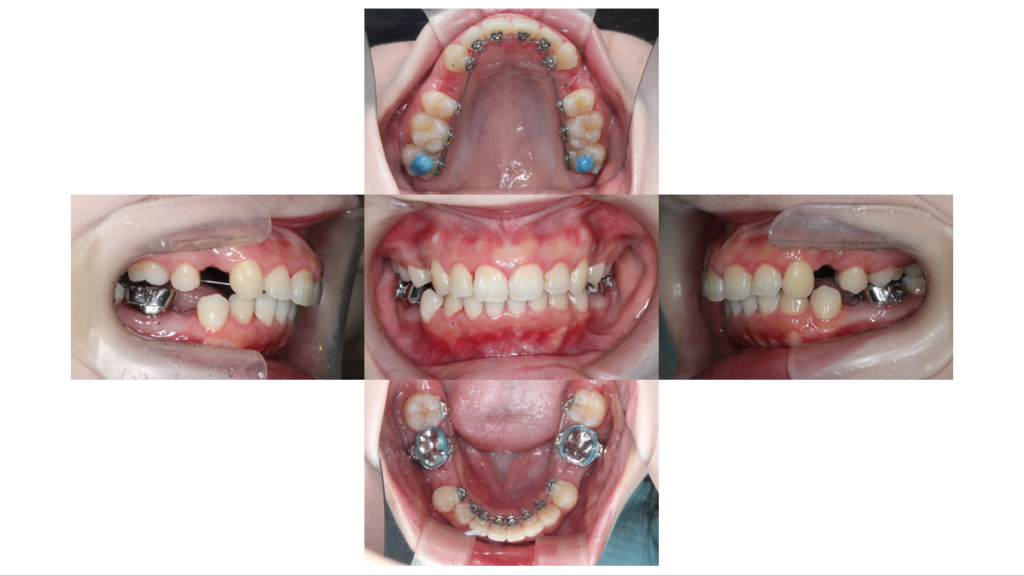

上下装置装着

上顎前突・裏側矯正の症例上下装置装着後の口腔内です

約3ヶ月経過

上顎前突・裏側矯正の症例約3ヶ月経過し、ガタつきが改善されてきました